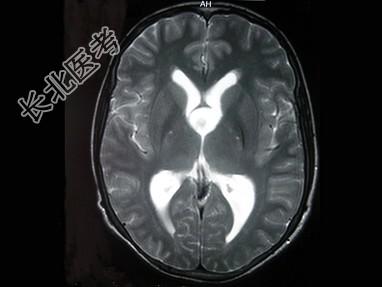

- 单项选择题女,29岁, 头痛、头昏10年,伴记忆力下降, 根据所提供图像,最可能的诊断是 ( )

A、胶样囊肿

B、蛛网膜囊肿

C、胶质瘤

D、室管膜瘤

E、表皮样囊肿